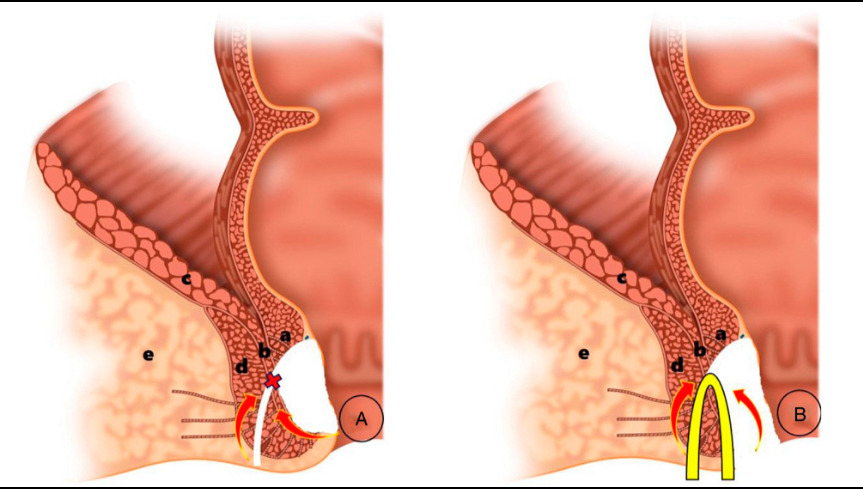

与其他术式相比,TROPIS 术的巧妙之处,正在于「绕开要害、精准拆隧道」;加上松弛挂线手术,这套组合术既能彻底清病灶,又最大程度保护括约肌这个「排便闸门」,是对付高位复杂性肛瘘的「利器」。

TROPIS(经肛括约肌间切开术)作为目前一种新兴的肛瘘保留肛门括约肌手术,其核心原理是:①经肛门切开肛门内括约肌,开放内外括约肌间隙,清除感染源。②保留外括约肌,减少对肛门控便的影响。③引流脓腔或瘘管,达到二期愈合。

该术式的核心优势在于:经肛内切开肛门内括约肌,完全敞开括约肌间隙,几乎不损伤肛门外括约肌,极大程度的保护肛门功能和肛周形态。

手术中,团队借着高清视野,绕开要害、精准拆「隧道」:既把瘘管和脓包清得干干净净,又没碰伤外层括约肌——这层肌肉是控制排便的关键,不损伤它,就守住了 「控便底线」;再用松弛挂线术引流剩余的脓腔和瘘管,让创面慢慢二期愈合,避免积液积脓。